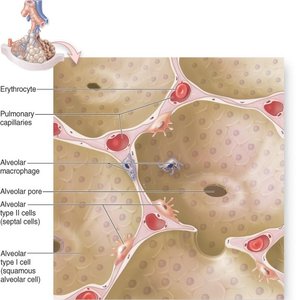

Alveoli are tiny air sacs where gas exchange occurs. They are surrounded by capillaries and have thin walls to facilitate diffusion.

Type I Alveolar Cells: Simple squamous cells forming the respiratory membrane.

Type II Alveolar Cells: Cuboidal cells that secrete surfactant to reduce surface tension.

Alveolar Macrophages: Remove debris and pathogens.

Alveolar Pores: Equalize air pressure and provide alternate air routes.